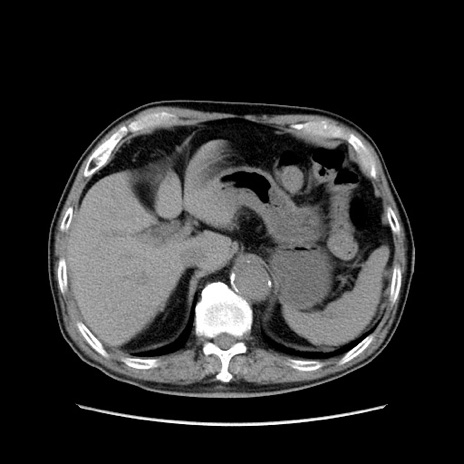

症例24(横断像)

【症例】80歳代男性

【主訴】左側腹部痛、嘔吐

【現病歴】本日早朝より左腹部に痛みあり。昼頃嘔吐認めたため、救急要請。

【既往歴】直腸癌(Mile手術)、胆摘

【身体所見】意識清明、BT 35.9℃、BP 221/93mmHg、SpO2 97%(RA) 、腹部:左ストーマ周囲に限局性の腹部膨隆あり。 膨隆部自発痛・圧痛あり・軟。

【データ】WBC 7700、CRP 0.09